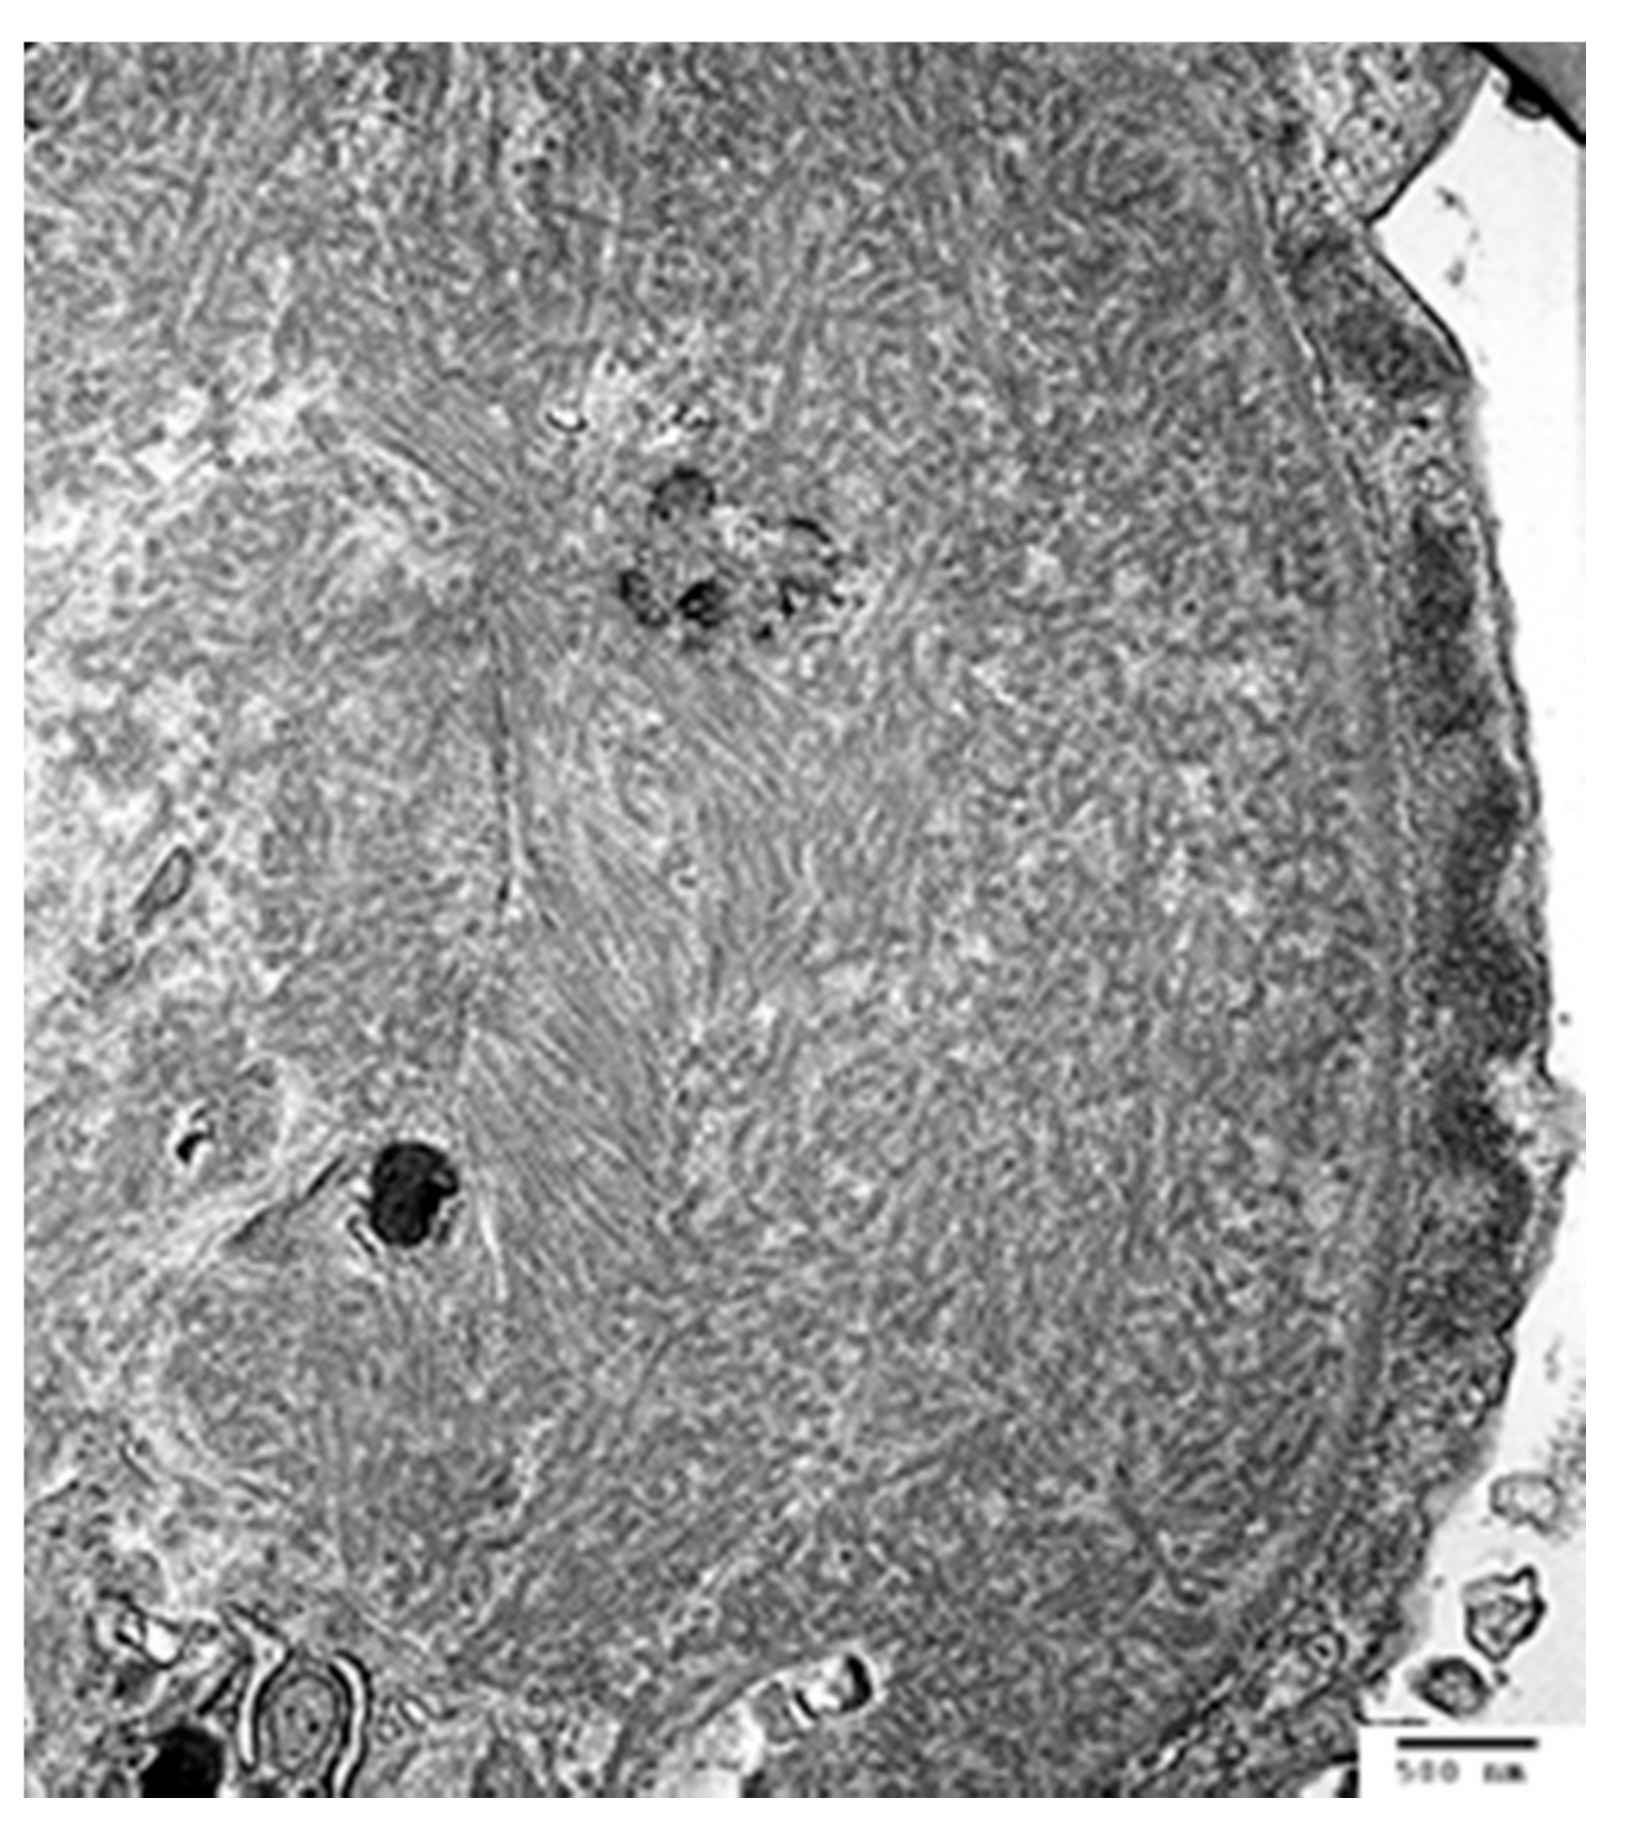

The diagnosis of amyloidosis requires a tissue biopsy showing the presence of amyloid fibrils. On light micrograph, amyloid most commonly forms amorphous deposits in the glomerular, tubulointerstitial, and/or vascular compartment, which are pale when stained with H&E and weakly positive with periodic acid-Schiff (PAS). As a result of the unique beta pleated sheet configuration, amyloid deposits show characteristic apple green birefringence under polarized light when stained with Congo red or yellow-green fluorescence with Thioflavin T [68]. The randomly arrayed, non-branching fibrils are 7–12 nanometers in diameter on electron micrograph (Figure 3).

Amyloid typing, to confirm AL type, is critical before treatment recommendations can be made. Typing by immunofluorescence microscopy is highly sensitive for AL amyloidosis, and shows bright, smudgy staining restricted to one light chain. In challenging cases, immunogold electron microscopy or liquid chromatography–tandem mass spectrometry on laser dissected deposits can be performed to confirm amyloid type [69].